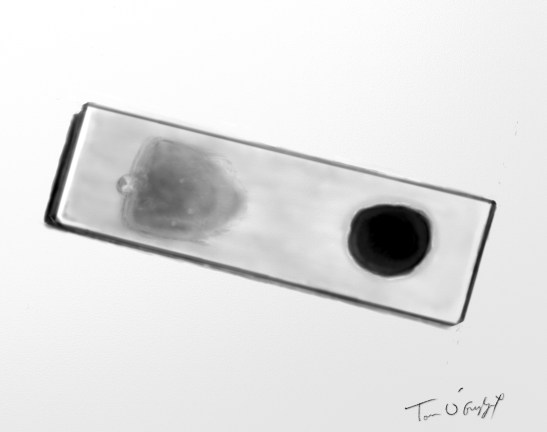

frottis sanguin à gauche et goutte épaisse à droite sur la même lame pour le diagnostic de paludisme au microscope

Il doit se faire en urgence, nécessitant la lecture d’une lame d’un frottis sanguin. En cas de négativité on utilise la technique de la goutte épaisse, par concentration du sang pour avoir plus de chances d’observer des parasites au microscope, d’identifier l’espèce et de quantifier la parasitémie. Sa sensibilité est nettement supérieure au frottis mais elle demande du temps, les deux méthodes sont souvent réalisées parfois sur la même lame. Le diagnostic au microscope optique est parfois difficile pour les trophozoïtes (formes en anneaux très similaires pour toutes les espèces).